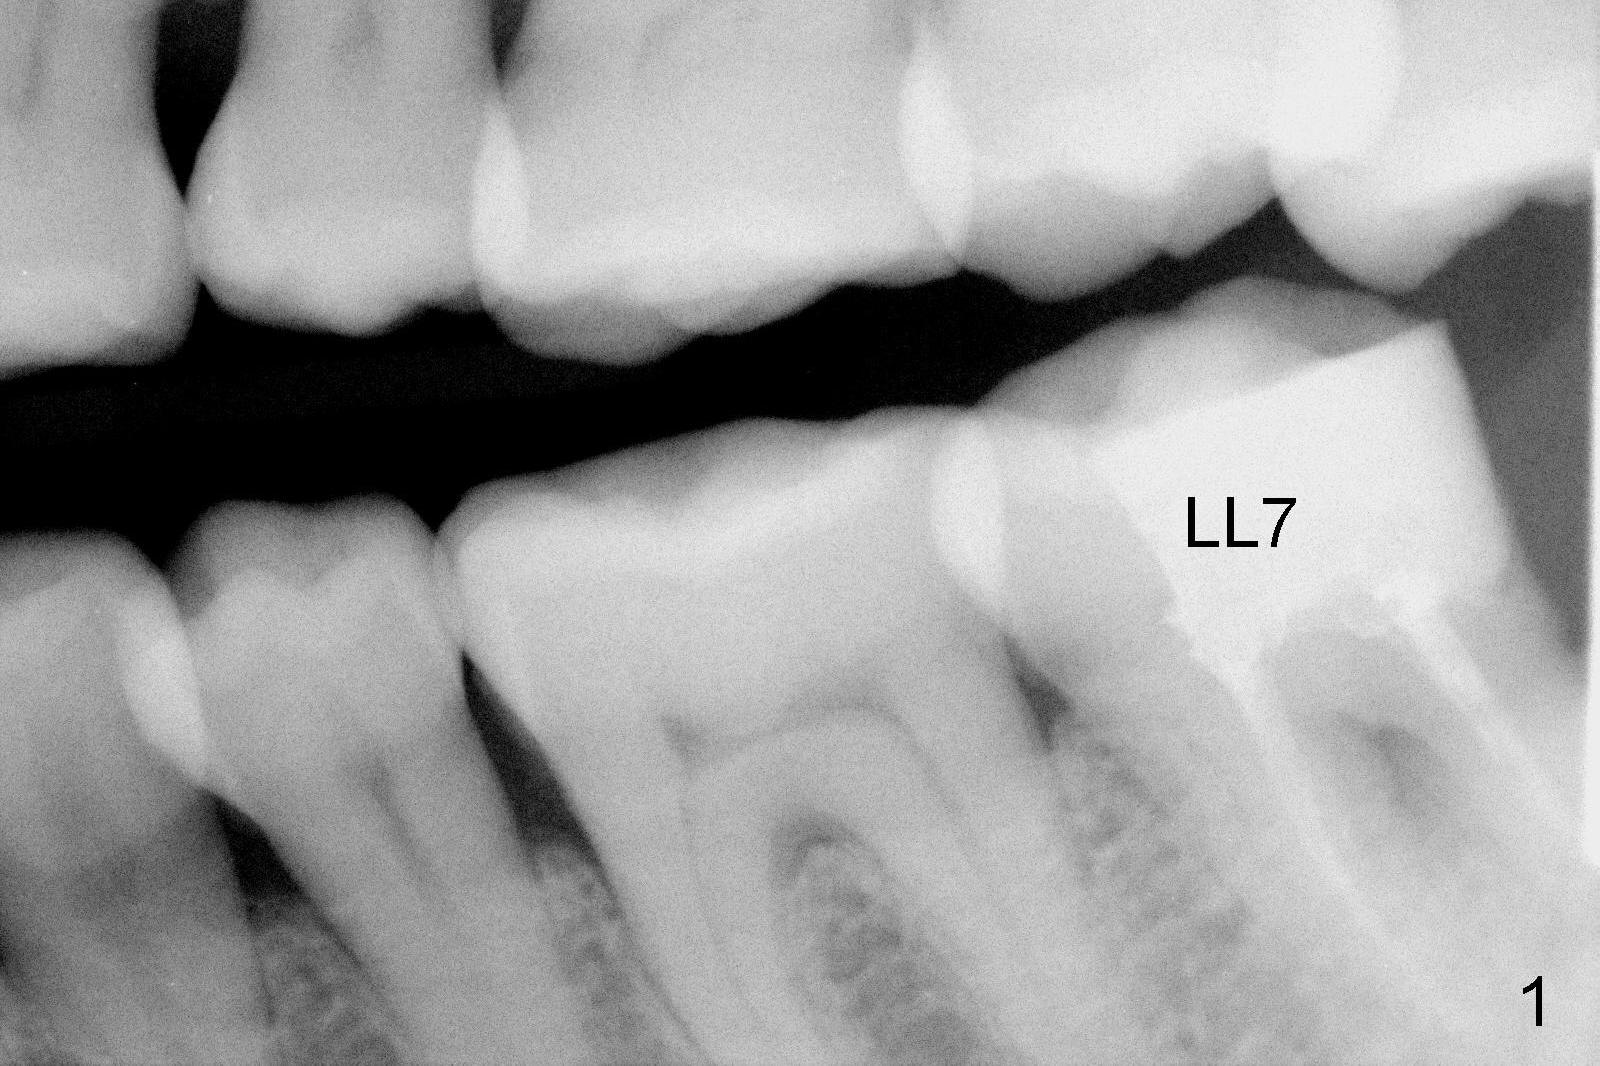

A 48-year-old lady is a dental phobic, requesting extraction of the lower left 2nd molar (Fig.1). She returns for implant placement 9 months post extraction (Fig.2). The ridge is mildly to moderately atrophic. It appears that a 5x12 mm implant is appropriate for the site (Fig.3). For safety, osteotomy is initiated at the depth of 10 mm; it appears that there is enough height for a 12 mm implant (Fig.4). The depth is controlled by drill stopper (Fig.5 S). Finally a 5x12 mm implant is apparently safely placed (Fig.6). A healing abutment is placed and the incision is sutured with 4-0 Chromic gut (Fig.7). Perio dressing is applied around the healing abutment for wound protection (Fig.8). It appears that the healing abutment (Fig.8': *) helps stabilize the perio dressing, which remains in place 1 week postop. When the perio dressing is removed, the wound around the healing abutment is healing (Fig.9). There is no bone loss around the implant 3 months postop (Fig.10 (H: healing abutment), or 16 months postop (i.e., 9 months post cementation, Fig.11,12). The patient complains of pain when she chews with the implant crown, but pain stops whenever she does not bite. Percussion does not elicit any discomfort. The gingiva is healthy. There is possibility of the buccal plate being thin or the lingual plate being perforated in the submandibular fossa. If the discomfort remains the same next 6 months, CBCT will be prescribed.